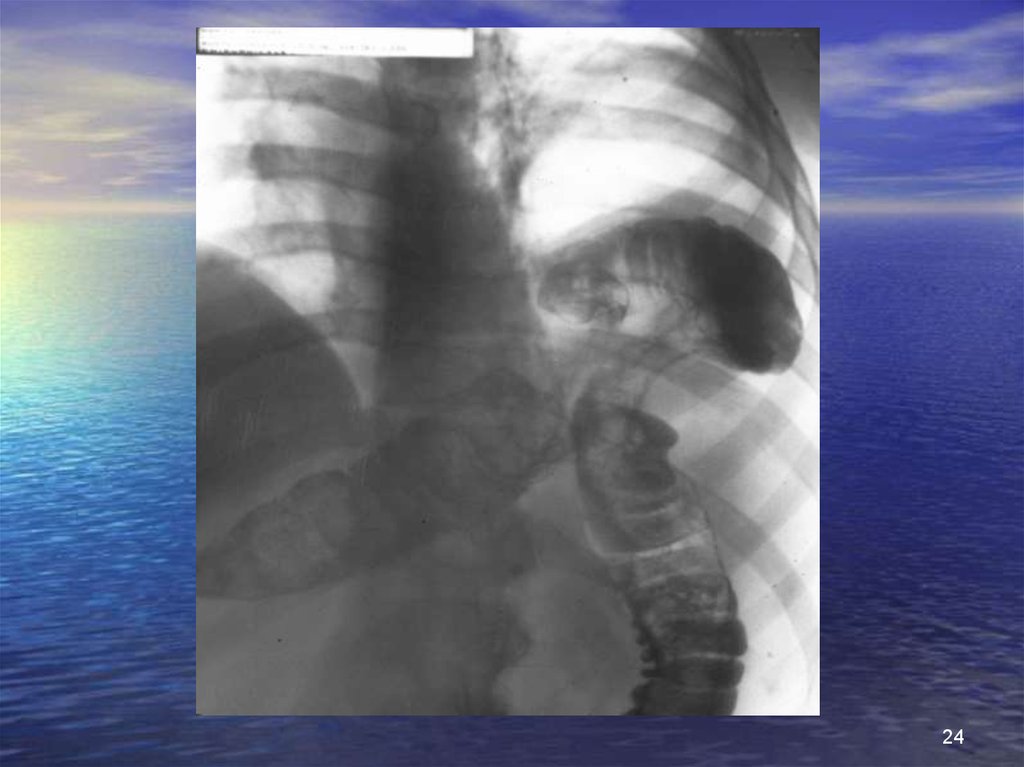

Разрыв диафрагмы (3)

рентгенологические исследования

• Очевидное повреждение диафрагмы

картина повышенной гидроаэрогенности внутри грудной клетки

грыжа с содержимым из полых органов

установка зонда;

ввести водорастворимый контраст;

картина затемненная: органы паренхимы

• Повреждения с трудной интерпретацией

поднят купол диафрагмы плохо визуализируется;

ателектазы;

гемо- или пневмоторакс;

затемнения базы легких